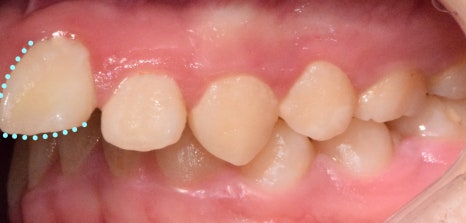

이번 케이스는

‘위턱이 많이 나온 상황’으로

측절치의 결손으로

위턱과 아래턱의 부조화가 나타났습니다.

처음에는

치아가 보이지 않을 정도로

많이 튀어나왔지만,

턱이 뒤로 들어가면서

올바른 형태로 찾아갈 수 있었습니다.